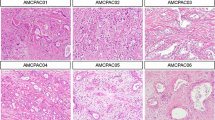

Tables 2 and 3 show the results of the grading of the cell lines. The grade 1 cell lines, Capan-1 and Capan-2, differed little in their features. The nuclei of the monomorphous cells showed homogeneous chromatin and one to four round nucleoli. The abundant cytoplasm contained many electron dense or lamellar mucin granules, Golgi complexes, and elements of rough endoplasmic reticulum. The cells were connected by numerous cell junctions such as desmosomes and junctional complexes. Networks of intermediate filaments were anchored to the desmosomes. Capan-1 cells formed many interdigitations with neighboring cells. Capan-2 cells had well developed microvilli and glycocalyx on their surface. In spheroids both cell lines revealed marked lumen formation. Capan-1 cells and to some extent Capan-2 cells showed a polarization towards the outer surface of the spheroids, with mucin granules in apical position and nuclei at the opposite side. The lateral plasma membranes at the apical pole of the cells were connected by regular junctional complexes (Fig. 1a).

Ultrastructural features of PDAC cell lines. a Spheroid of Capan-2 cells showed polarity toward the surface, a number of microvilli and cell junctions, glycocalix on the surface. b Colo-357 cells in spheroid showed many microvilli, mucin granules, well developed Golgi apparatus and endoplasmic reticulum. c HPAF-2 cells in spheroid formed lumina with microvilli, numerous cell junctions. Note the markedly irregular nucleus with crude chromatin structure and membrane invagination. d MiaPaCa-2 cells in monolayer culture exhibited poorly developed membrane structures, cytoplasmic organelles and few mucin granules. Original magnification, ×3000

The grade 2 cell lines exhibited marked heterogeneity from cell line to cell line. The most striking difference between these lines and the grade 1 cell lines was the pronounced cellular and nuclear polymorphism. The nuclei of the polymorphic cells were irregular and sometimes highly segmented, occasionally with crude chromatin structure and with up to four nucleoli. In some cell lines a reduced number of interdigitations (A818-4, Aspc-1, Colo357) and desmosomes (Aspc-1, Colo357) was noted. In general the cells were well equipped with cell organelles, i.e., Golgi complexes, rough endoplasmic reticulum, and mucin granules. Lumen formation was seen in the spheroids, but the lumina were smaller and more irregular than in grade 1 spheroids. None of the grade 2 spheroids showed signs of polarization (Fig. 1b, c).

The grade 3 cell lines showed significantly fewer cell organelles, specialized membrane structures and mucin granules than the grade 2 cell lines. The cytoplasm contained elements of rough endoplasmic reticulum which were rarely organized in parallel structures. Golgi complexes were only seen in PancTu-I cells. Interdigitations were completely absent. Interestingly, PancTu-I spheroids formed well defined lumina. MiaPaCa-2 cells were not able to generate spheroids. We interpreted this phenomenon as loss of the capability to form cell-cell contacts and hence considered the MiaPaCa-2 cell line to be the most poorly differentiated line (Fig. 1d).